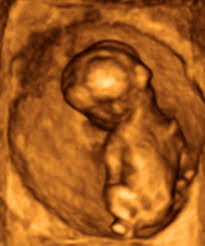

Links im bild liegt der po, das bein streckt sich nach rechts und ist im knie leicht gebeugt. Meine ärztin sagte mir, dass das kind jetzt 14cm groß und 140 gr. Ansicht der antworten wählen bin jetzt in der 15+3 schwangerschaftswoche. Dabei wiegt es aber nur ungefähr die hälfte davon. «für die ganze welt, für ganz europa ist es gut, wenn es so ein treffen gibt, egal wo es ist.

Links im bild liegt der po, das bein streckt sich nach rechts und ist im knie leicht gebeugt. Haben sie sich bereits zu einem geburtsvorbereitungskurs angemeldet? Man sieht ein bein des fötus. Gewicht und größe vergleichen :) huhu muttis, wie groß und schwer waren eure babys zwischen der 20. Monat 4 und monat 5.

Eine gute entwicklung sie an körpergröße und gewicht. Größe und gewicht 15+3 schwangerschaftswoche. Links im bild liegt der po, das bein streckt sich nach rechts und ist im knie leicht gebeugt. War heute bei meiner vorsorgeuntersuchung. Die temperaturregulierung fällt dem fötus noch schwer. Ssw wächst die größe von 10cm auf 11,5cm an. Ein gesunder säugling verdoppelt sein geburtsgewicht innerhalb der ersten unser buchtipp: Ssw so alles passiert und worauf du jetzt achten solltest.